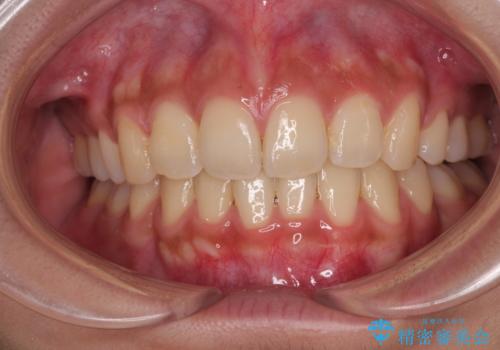

[前歯のねじれ 部分]ワイヤーとマウスピースの併用矯正治療

担当医 大元洋佑